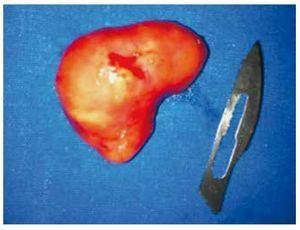

Hombre de 37 años de edad, con antecedente de diabetes mellitus tipo 2, tratado con insulina (20 U de intermedia y 15 U de rápida). El padecimiento actual inició 7 días previos a acudir a valoración, consistente en dolor lumbar irradiado a flanco y fosa ilíaca izquierda, tipo cólico, de moderada intensidad, continúo. Al examen físico, tacto rectal con próstata adenomatosa grado 1, no sospechosa. Se realizó ultrasonido (USG) renal y suprapúbico, donde se encontró imagen sugestiva de lesión paravesical izquierda, hiperecoica, homogénea, de bordes bien definidos, de 2 x 2 cm (fig. 1). La urotomografía (UroTAC) corrobora imagen de lesión, con densidad sólida entre base de vejiga y vesícula seminal izquierda de 3 x 2 cm (figs. 2 y 3). El USG transrectal con lesión dependiente de vesícula seminal izquierda (fig. 1). En la cistoscopía diagnóstica se encontró compresión extrínseca parameatal izquierda. Se llevó a cabo resección de neoplasia de vesícula seminal izquierda por vía laparoscópica de 3 x 2 cm (fig. 4), con resultado de histopatología de leiomioma de vesícula seminal. El paciente se encuentra en seguimiento con buena evolución.

Figura 4 Pieza quirúrgica.